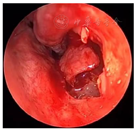

入院后完善术前常规检查,于次日在局麻下行切开引流术,阿替卡因肾上腺素行21-22前庭沟黏膜下局部浸润麻醉,麻醉显效后,自21-22前庭沟处切开黏膜及黏膜下层至囊腔约3 mm水平切口,见大量黄色分泌物溢出,取部分脓液做细菌培养,大量生理盐水冲洗至冲洗,留置橡皮引流条,术后常规予以抗生素控制感染。4 d后检查前庭沟切口处已愈合。经耳鼻咽喉科与口腔颌面外科会诊,决定行鼻内镜下左侧鼻底、下鼻道共同开窗肿物切除术。术中先用彭氏电刀电凝左侧鼻底及下鼻道隆起处黏膜(图5),剥离子自隆起处外侧刺破黏膜进入囊腔,见大量囊液流出,囊液呈浅褐色,略浑浊,吸净囊液后,向后扩大开窗口,保留后部黏膜瓣。剥离部分囊壁送病理检查,清除病变组织后,发现位于囊腔前下壁的不完全的骨间隔隆起(图6)。剥离子在囊肿的左侧上部探查见上颌窦内下骨质缺损,由此刺破软组织进入上颌窦,见有黏液涕流出,扩大上颌窦开窗口,动力系统清除病变组织,使囊肿腔与上颌窦形成一个腔(图7),修剪后部蒂瓣,使之正好贴敷于囊腔后壁(图8),反复生理盐水冲洗术腔,检查无残留,膨胀海绵填塞。手术过程见视频。手术顺利,术后继续行抗生素控制感染,48 h抽出鼻腔膨胀海绵,检查见鼻底及上颌窦开窗口开放良好,腔内有少许血性分泌物,黏膜略水肿。术后病理镜下见被覆鳞状上皮,间质内见急慢性细胞浸润(图9)。术后4 d患者康复出院。